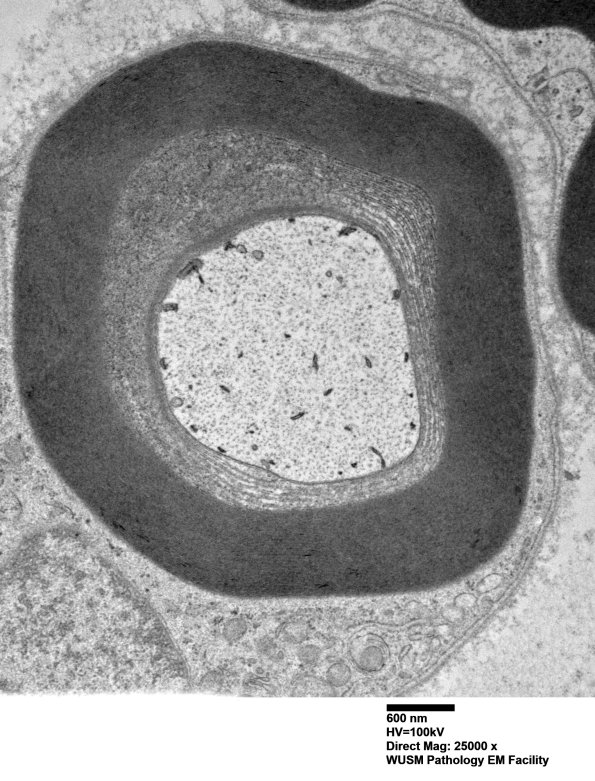

Extensive myelin alteration in peri-axonal inner myelin loops. (electron micrographs)